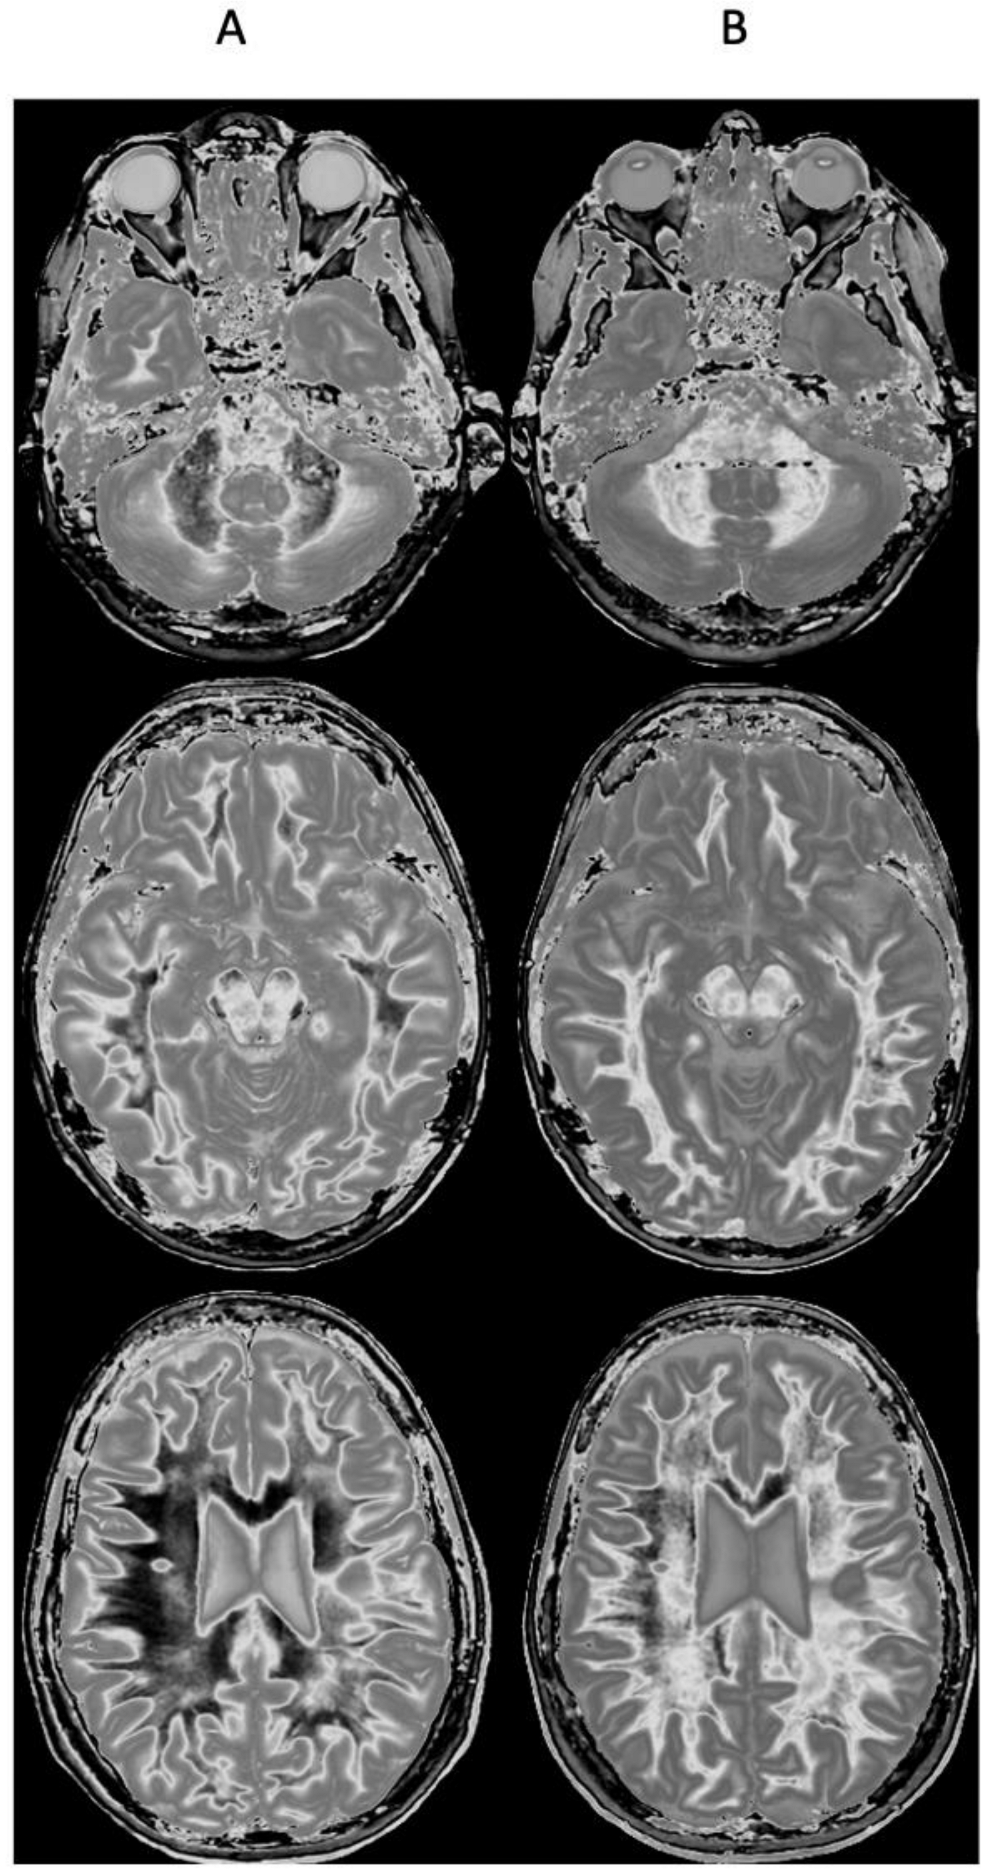

Figure 9 and Figure 10 show a 38-year-old patient with MS in remission (Figure 9A and Figure 10A, left columns) and during a relapse two years and five months later (Figure 9B and Figure 10B, right columns) imaged with the same narrow mD dSIR sequence. Figure 9 shows three positionally matched lower levels in the brain and Figure 10 shows two positionally matched higher levels in the brain. White matter shows a generally low signal during remission (whiteout sign grade 1–2) (Figure 9A and Figure 10A), and a high signal (whiteout sign grade 4–5) during the relapse (Figure 9B and Figure 10B). The multiple levels within the brain show the wide distribution of the high grade whiteout sign in the cerebellar and cerebral hemispheres, as well as in the brainstem. No evidence of a whiteout sign was seen on the corresponding T2-FLAIR images.

Figure 9.

Thirty-eight-year-old female patient with MS in remission (A, left column) and during a relapse (B, right column) two years and five months later. Matching narrow mD dSIR images at three lower levels in the brain. In remission (left column), there are bilateral symmetrical areas of low signal in the white matter of the cerebellar and cerebral hemispheres. The corresponding areas show increased signal during the relapse (right column) consistent with a grade 4–5 (out of 5) whiteout sign. No evidence of a whiteout sign was seen on the T2-FLAIR images.

Figure 10.

Thirty-eight-year-old female patient with MS in remission (A, left column) and during a relapse (B, right column) two years and five months later (same case as in Figure 9). Matching narrow mD dSIR images at two higher levels in the brain. In remission, white matter shows a low signal (left column). This is increased during the relapse in a bilateral symmetrical distribution consistent with a grade 4–5 (out of 5) whiteout sign (right column). No evidence of a whiteout sign was seen on the T2-FLAIR images.